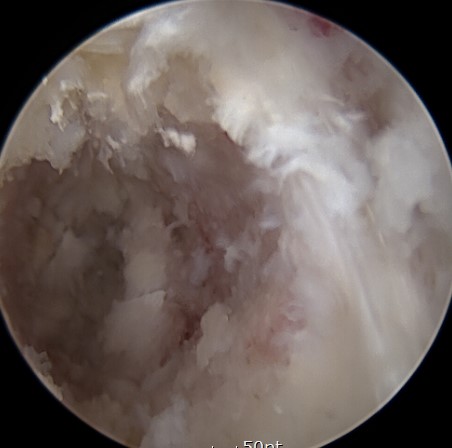

내시경으로 감압과 동시에

추간공을 확공하니

신경통로에 대한 확보 및

디스크를 제거하고

걷어낸 뒤

뼈 이식을 통해 공간을 다지구요

케이지를 삽입하여

수술을 마치게 됩니다